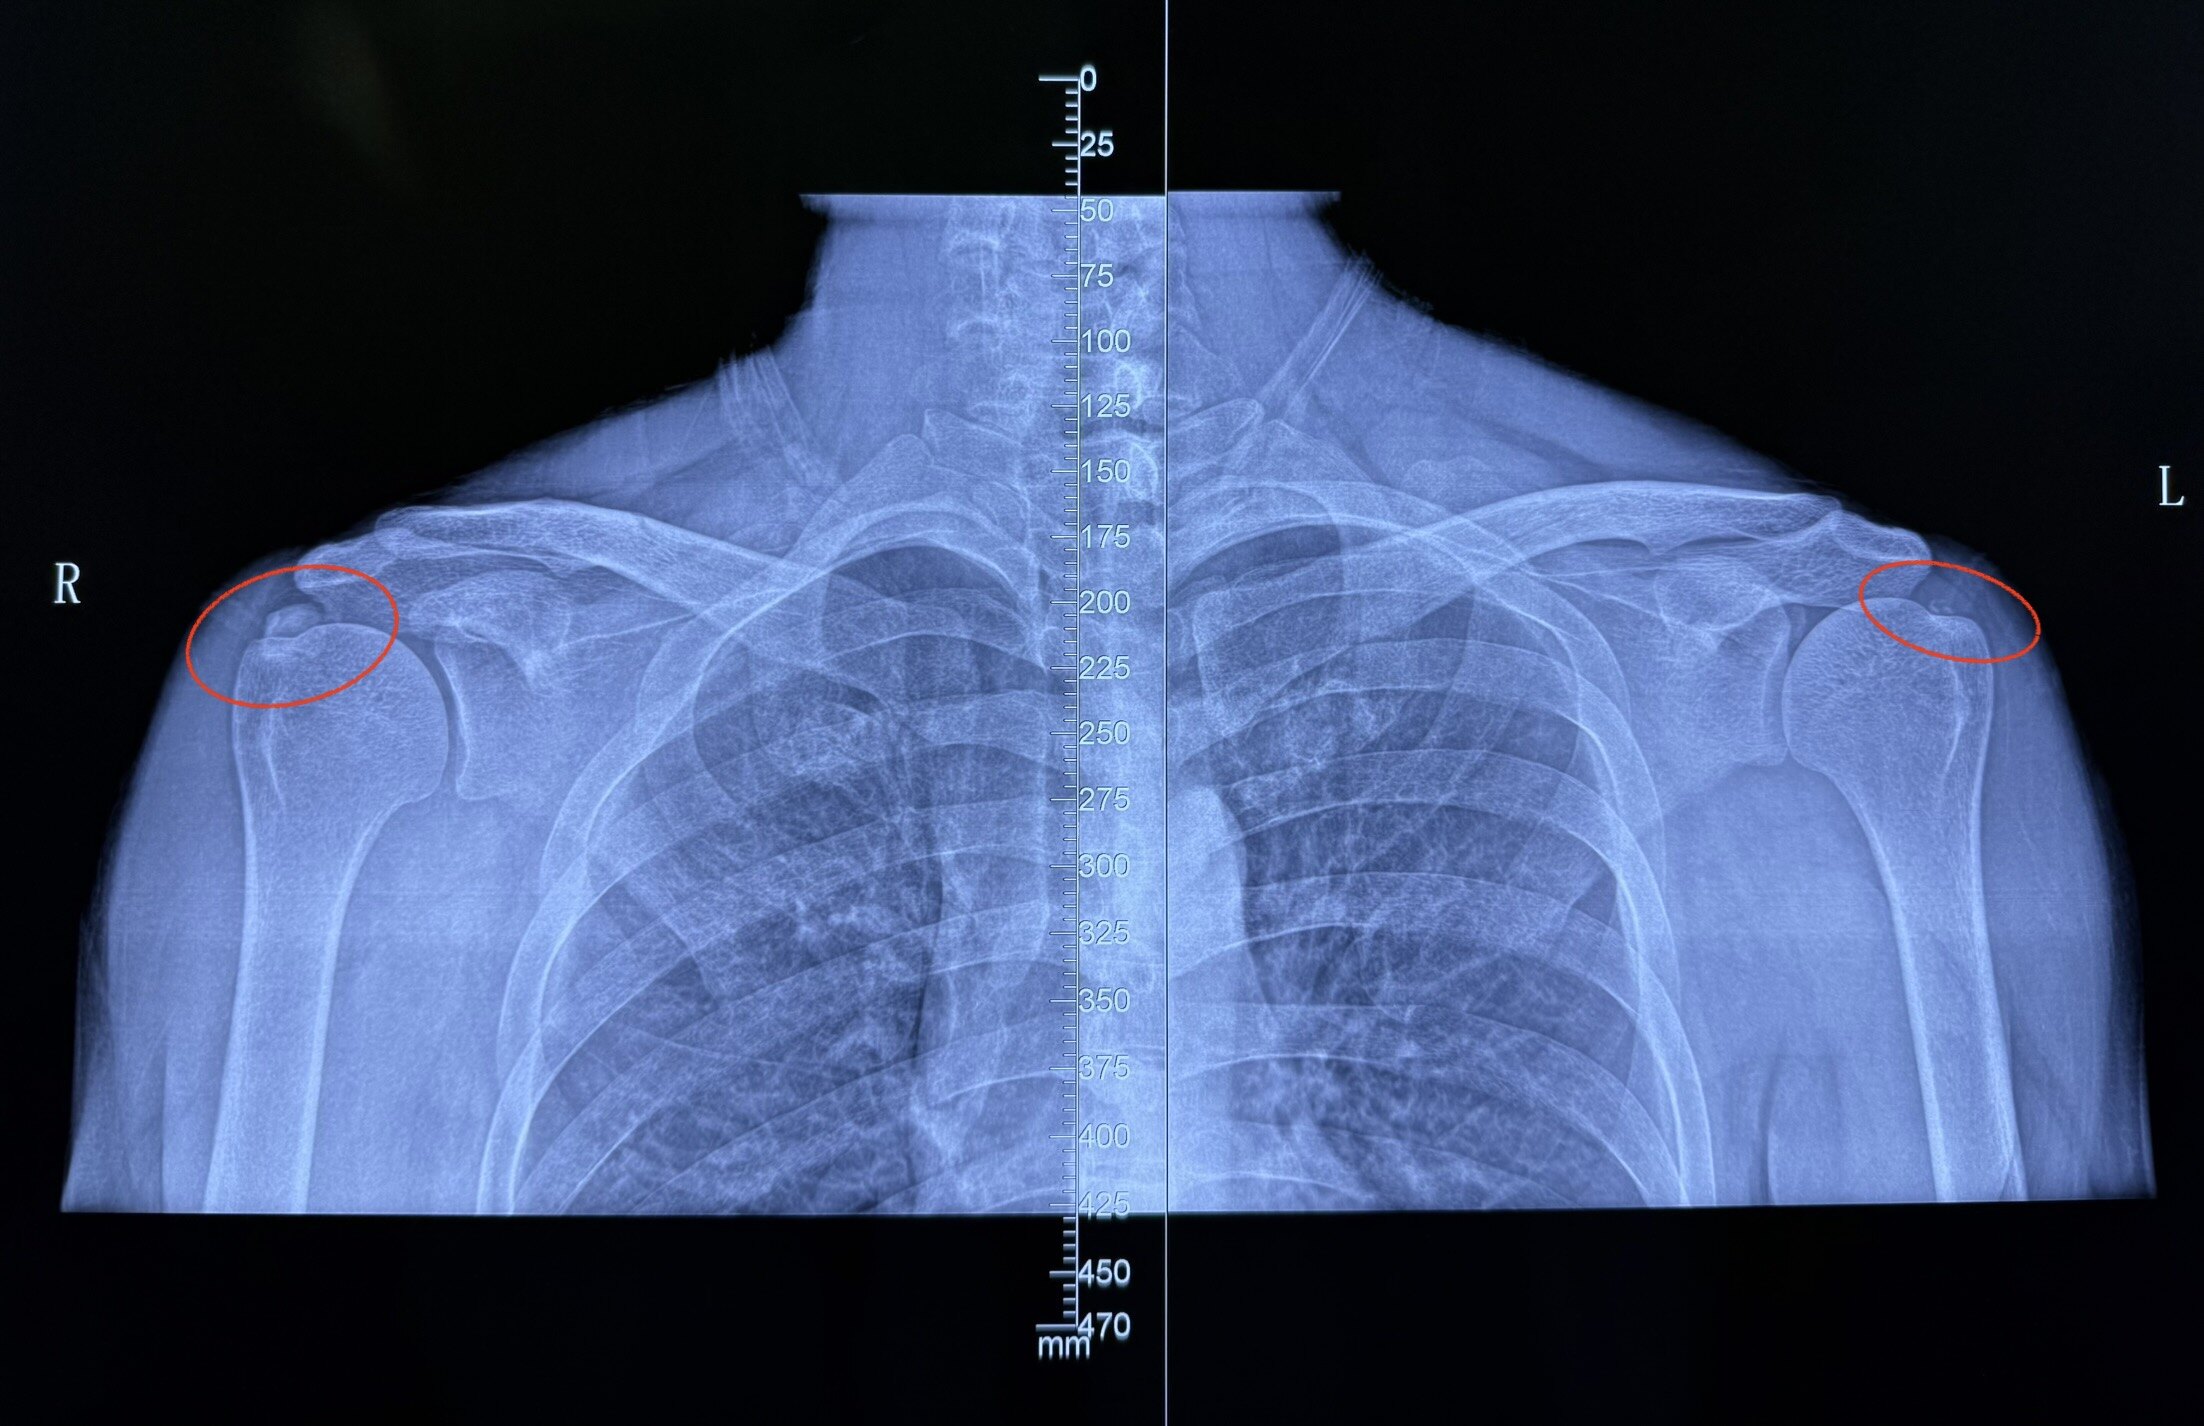

为什么为什么两个肩膀肩峰处一个高一个平缓,为什么啊?

图片尺寸2908x3460